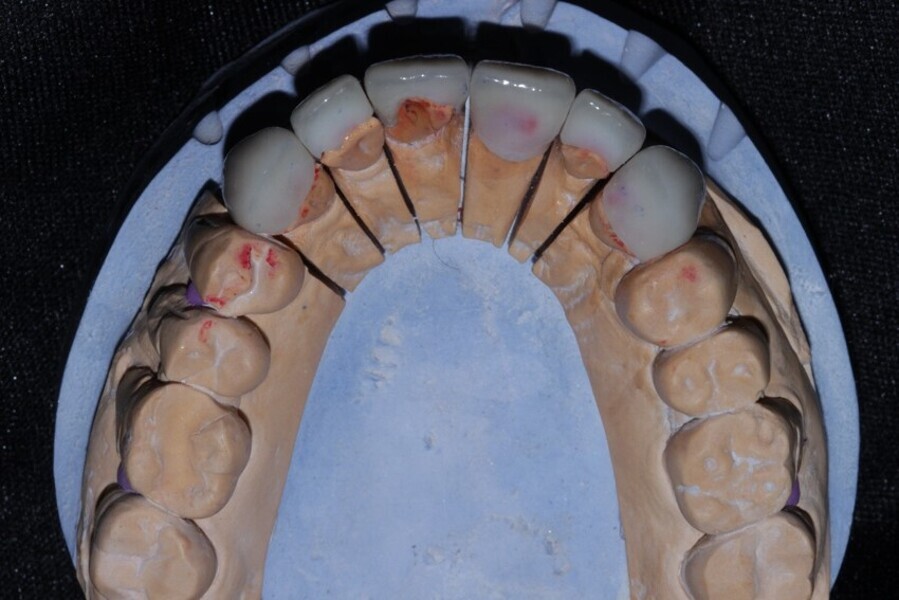

Figure 21 Palatal view of upper anterior emax 2 layered restorations all veneers except 21